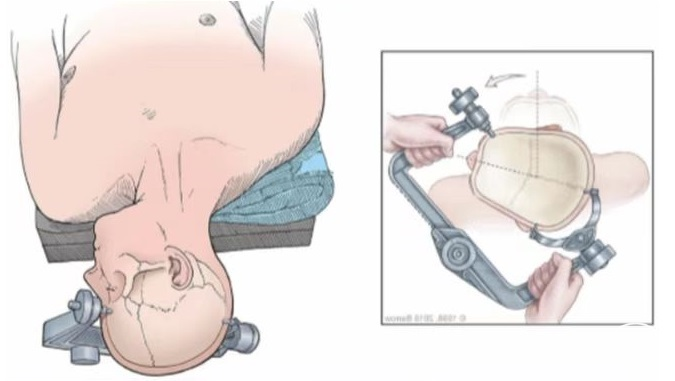

▼2.体位

通常采用健侧俯卧位,腋下垫起,头部下垂15°并向健侧旋转10°,颈部稍前屈,使下颌距胸骨约2横指,患侧乳突与手术台面大致平行并位于最高位置。患侧肩部用肩带轻拉向床尾端,使颈肩角>100°,确保手术操作不受肩部阻挡影响,需注意不可牵拉过重,以免造成臂丛神经损伤。

成人以头架固定,亦可用胶带将头位固定在床台,可无需头架固定。